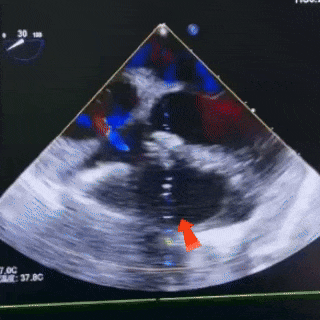

4.室间隔室上嵴回声连续中断。CDFI:室水平见收缩期高速左至右过隔分流信号,束宽约2.9mm,CW:4.21m/s ,PG:71mmHg。

缺损情况:室间隔室上嵴回声连续中断,室水平见收缩期高速左至右过隔分流信号,束宽约2.9mm。

左盘展开

展开左盘

使左盘贴靠于室间隔